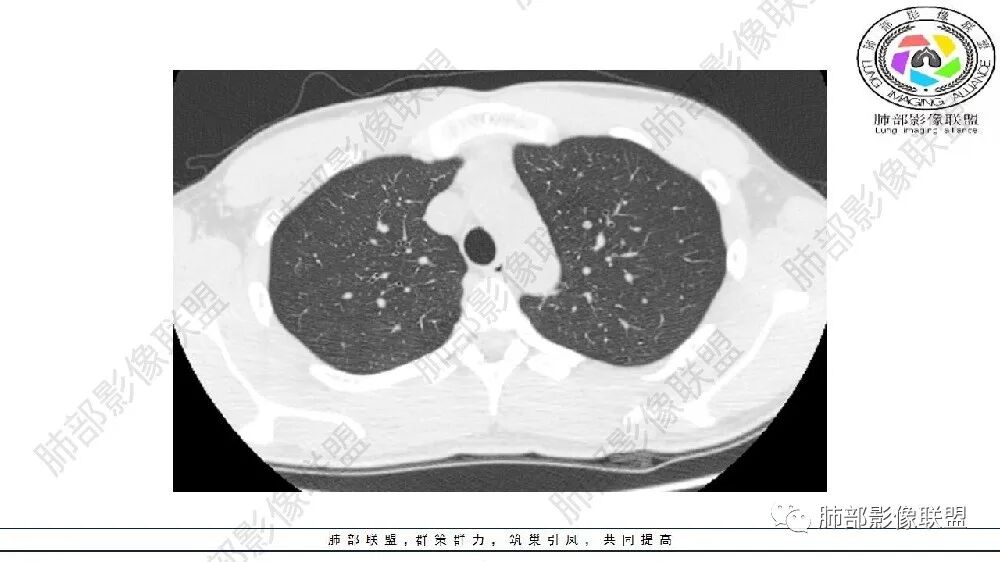

左肺下叶多发大小不等囊腔,部分有粘液栓,周围伴有磨玻璃影,左肺下叶基底干支气管未见,双肺尖可见多发局限性透亮区,青年男性,考虑先天性气道或肺部发育畸形,支气管闭锁?CPAM?鉴别肺隔离症。

左肺下叶多发薄壁囊性病灶,血管贴边,并多发增粗的血管,还有一些斑片影,磨玻璃影;两肺尖也有薄壁囊性病灶;病史咳嗽咳痰,痰中带血,跟老师们考虑肺隔离症伴感染,鉴别LIP

常规思路: 20岁,肺部出现低密度病灶:多半要考虑先天性病变;其次就是坏死空洞。先天性:肺气肿、囊腺瘤样畸形、闭锁、隔离、支气管扩张,这些病灶符合肺气肿,低密度,胸膜下,无壁。

闭锁?附近没有大片肺气肿,不符合。为啥没有一元论?因为上肺病灶与左下叶病灶表现完全不同,一个是单纯低密度影,无壁;一个是管状+血管畸形

估计上肺病灶不会处理,所以忽视掉